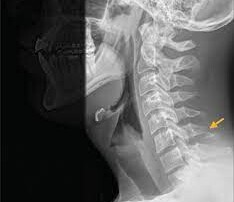

The car crash that changed my life

The head-on collision with a wrong way drunk driver occurred at the midway point between Phoenix and Payson. Read more.